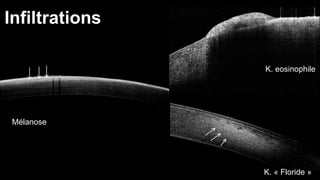

Infiltrations

Mélanose

K. eosinophile

K. « Floride »